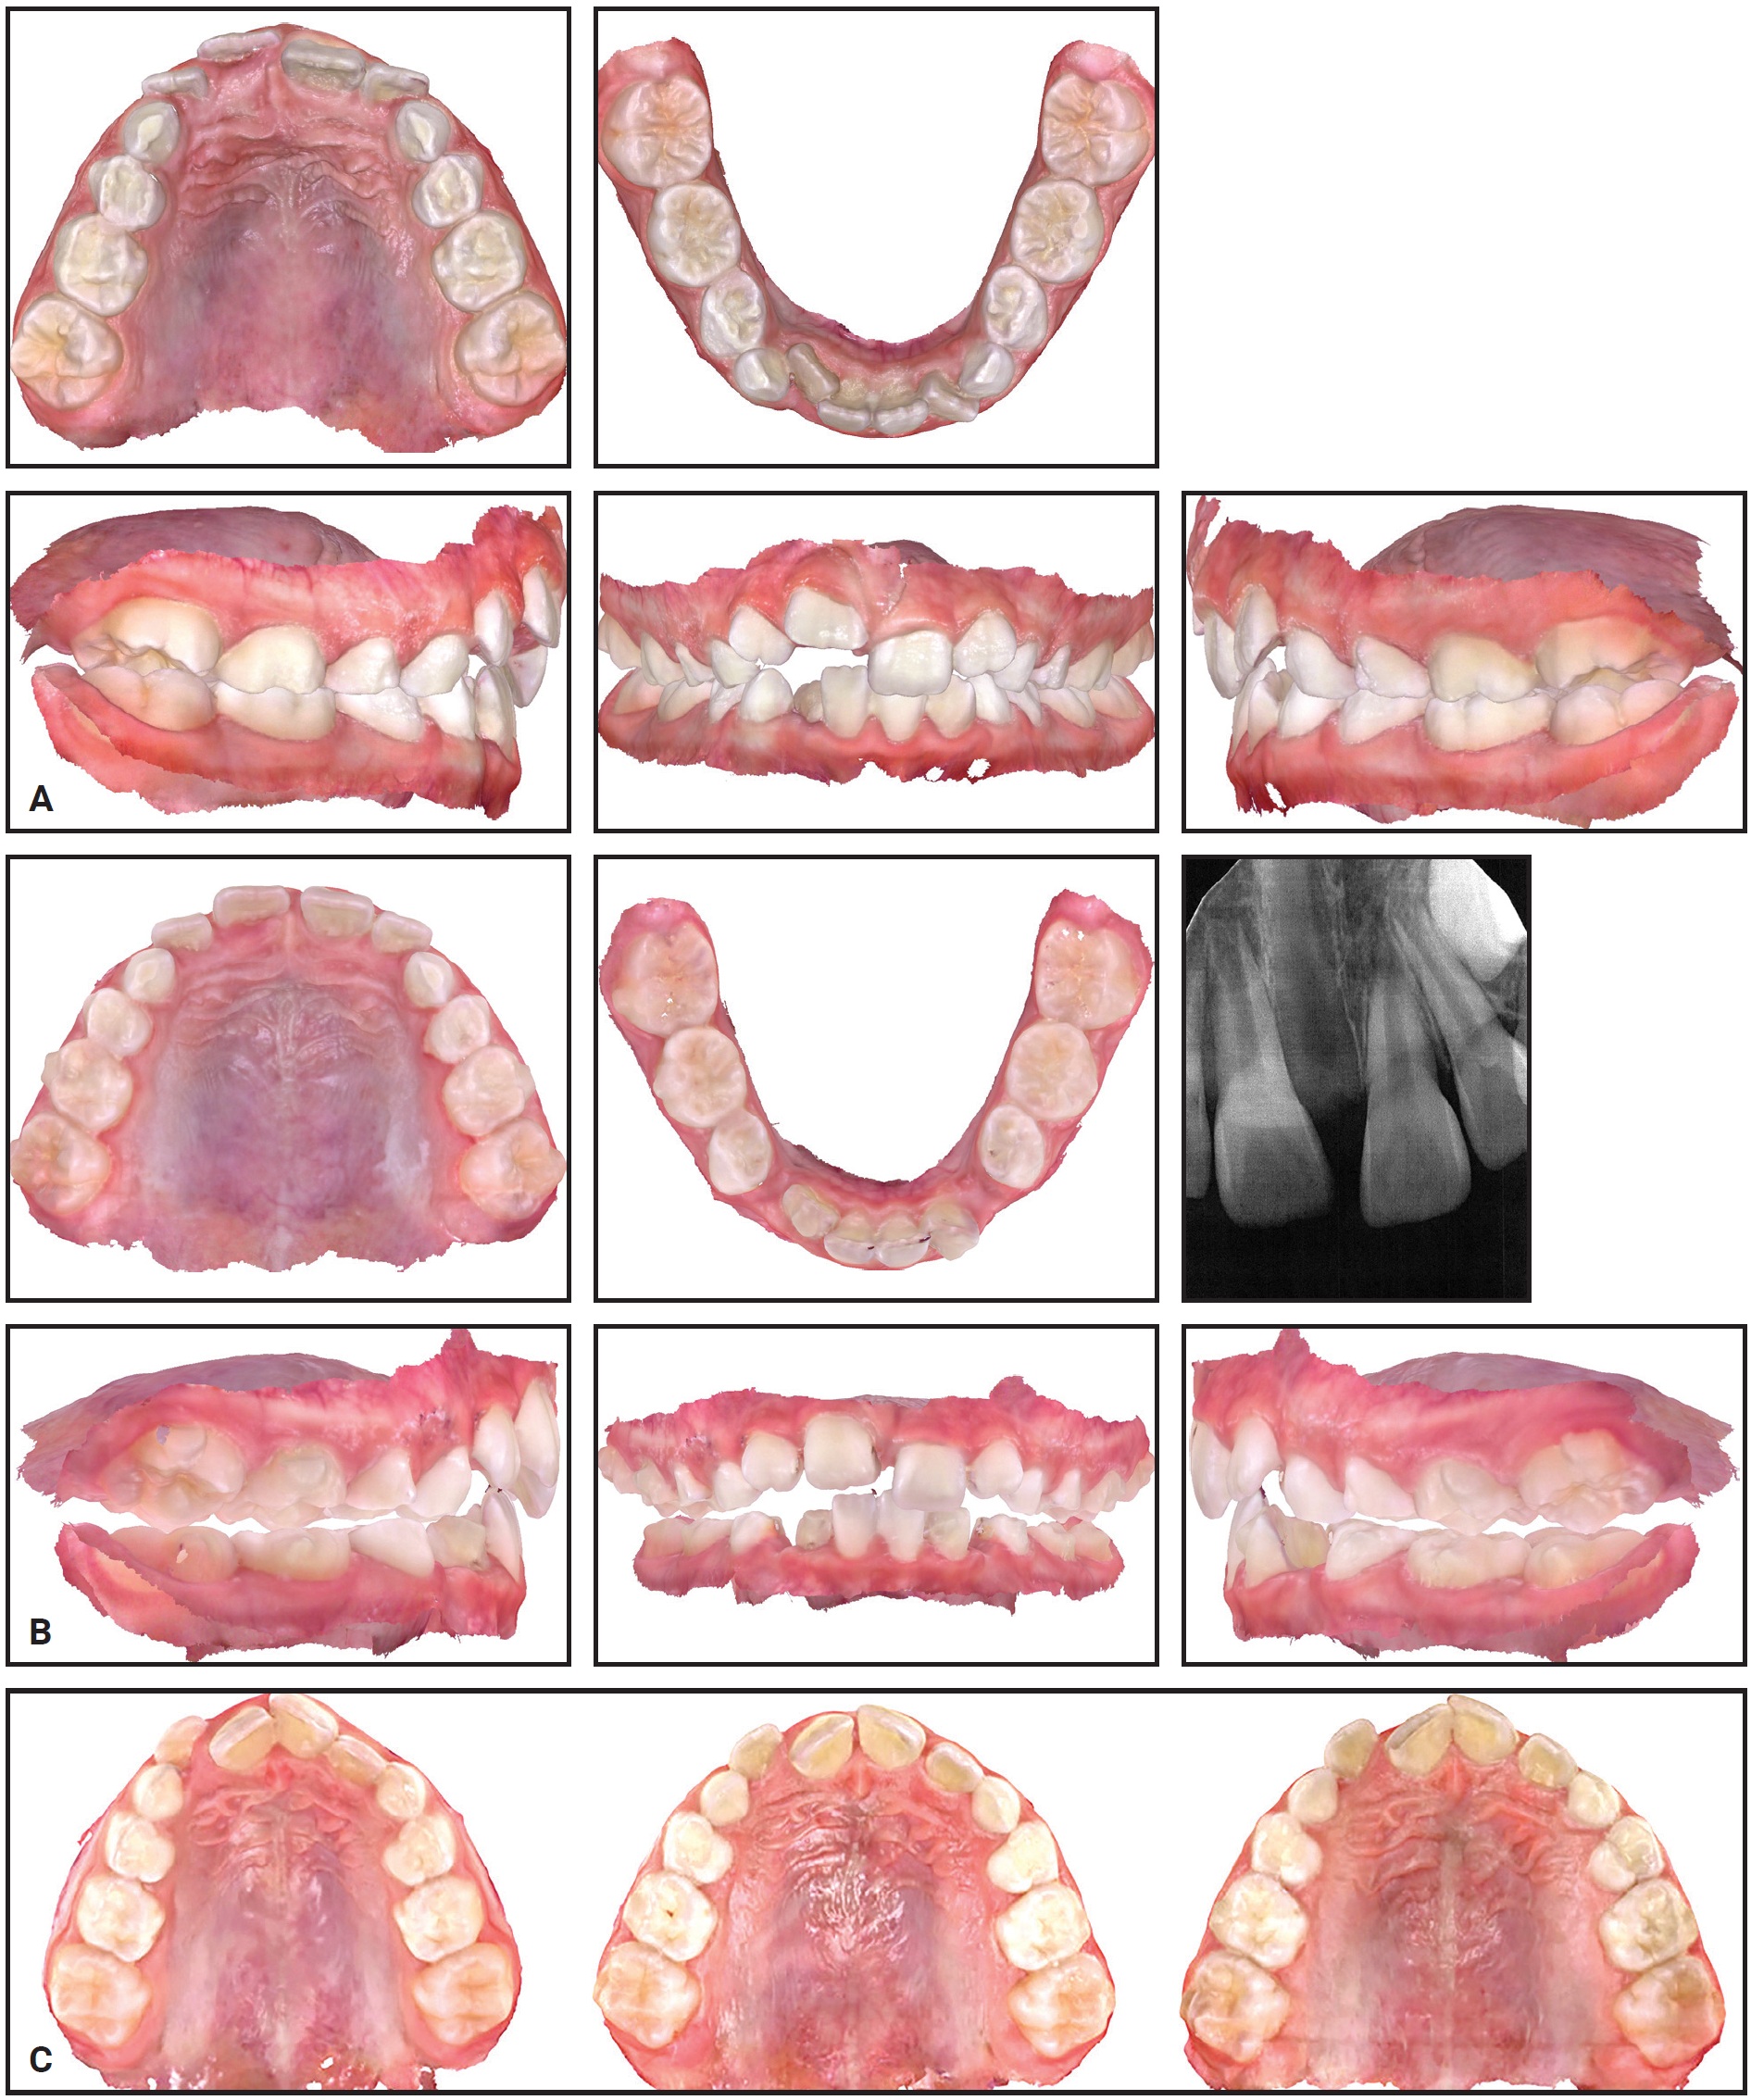

An 8-year-old female presented with maxillary constriction and blocked-out upper lateral incisors (Fig. 5). The panoramic radiograph revealed insufficient space for the developing upper canines. Maxillary expansion was recommended as a first phase of treatment to facilitate alignment of the upper incisors and create more space for the permanent canines.

After the patient wore 32 of 34 prescribed IPEs, which were changed daily, a periapical radiograph demonstrated sutural expansion. Holding expanders were then worn for six months to maintain the results.

Fig. 5 Case 2. A. At beginning of treatment. B. After 32 of 34 prescribed stages of expansion with IPE. C. Progress of expansion: beginning of treatment (left), after expansion (center), and after four months of retention (right).